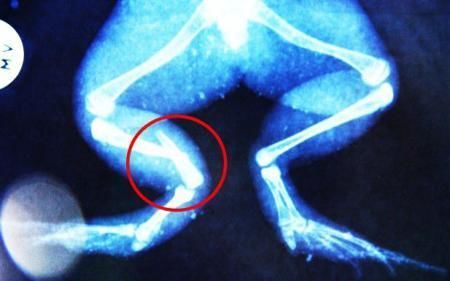

環(huán)球網(wǎng)4月2日?qǐng)?bào)道 據(jù)《每日郵報(bào)》報(bào)道,上個(gè)月,南非大牛蛙布魯萊的右小腿被鄰居家的一只狗咬到,導(dǎo)致粉碎性骨折,現(xiàn)在經(jīng)過(guò)2個(gè)小時(shí)的手術(shù),它的斷腿已經(jīng)被接上,它也因此成為有史以來(lái)第一只通過(guò)外科手術(shù)用鋼針接上斷腿的青蛙。

布魯萊的主人,居住在南非約翰內(nèi)斯堡附近的62歲的安妮·米恩斯說(shuō):“我對(duì)這只青蛙如此關(guān)心,人們一定認(rèn)為我瘋了,但是我無(wú)法眼睜睜看著它那么痛苦。青蛙因其靈活的腿腳而著稱(chēng),一想到布魯萊的腿里要留下一個(gè)薄金屬片,我就感到心痛。然而我知道,如果不進(jìn)行手術(shù),布魯萊以后就沒(méi)辦法動(dòng)彈了。因此我匆匆趕到獸醫(yī)那里,央求他給這只可憐的青蛙動(dòng)手術(shù)。這位獸醫(yī)整天救助小貓小狗,他很難理解為什么我這么擔(dān)心一只青蛙,但是最終他還是答應(yīng)了給布魯萊做手術(shù)。手術(shù)后是幾個(gè)小時(shí)的焦急等待,我們希望它能快快蘇醒過(guò)來(lái)。不過(guò)現(xiàn)在它的傷口已經(jīng)愈合,又能在花園里跳來(lái)跳去了。X光照射顯示,它會(huì)恢復(fù)的跟以前一樣。”

野生生物專(zhuān)家安妮經(jīng)常為學(xué)校寫(xiě)教材,她認(rèn)為這是人類(lèi)第一次通過(guò)手術(shù)給一只青蛙接斷腿。在手術(shù)開(kāi)始階段,獸醫(yī)把少量給狗用的麻醉藥注入到這只青蛙體內(nèi),讓它失去知覺(jué)。然后他在布魯萊的斷腿上切開(kāi)一個(gè)小口,把一根小鋼針植入腿里。最后獸醫(yī)給它縫了9針,把切口縫合在一起。僅僅幾周后,布魯萊就能在安妮家附近活動(dòng)了。這只青蛙大約已有25歲,主要以嚙齒動(dòng)物、蛇和其他青蛙為食。布魯萊所屬的牛蛙種群正在不斷減小,目前只能在非洲南部的濕地里才能看到這種青蛙。